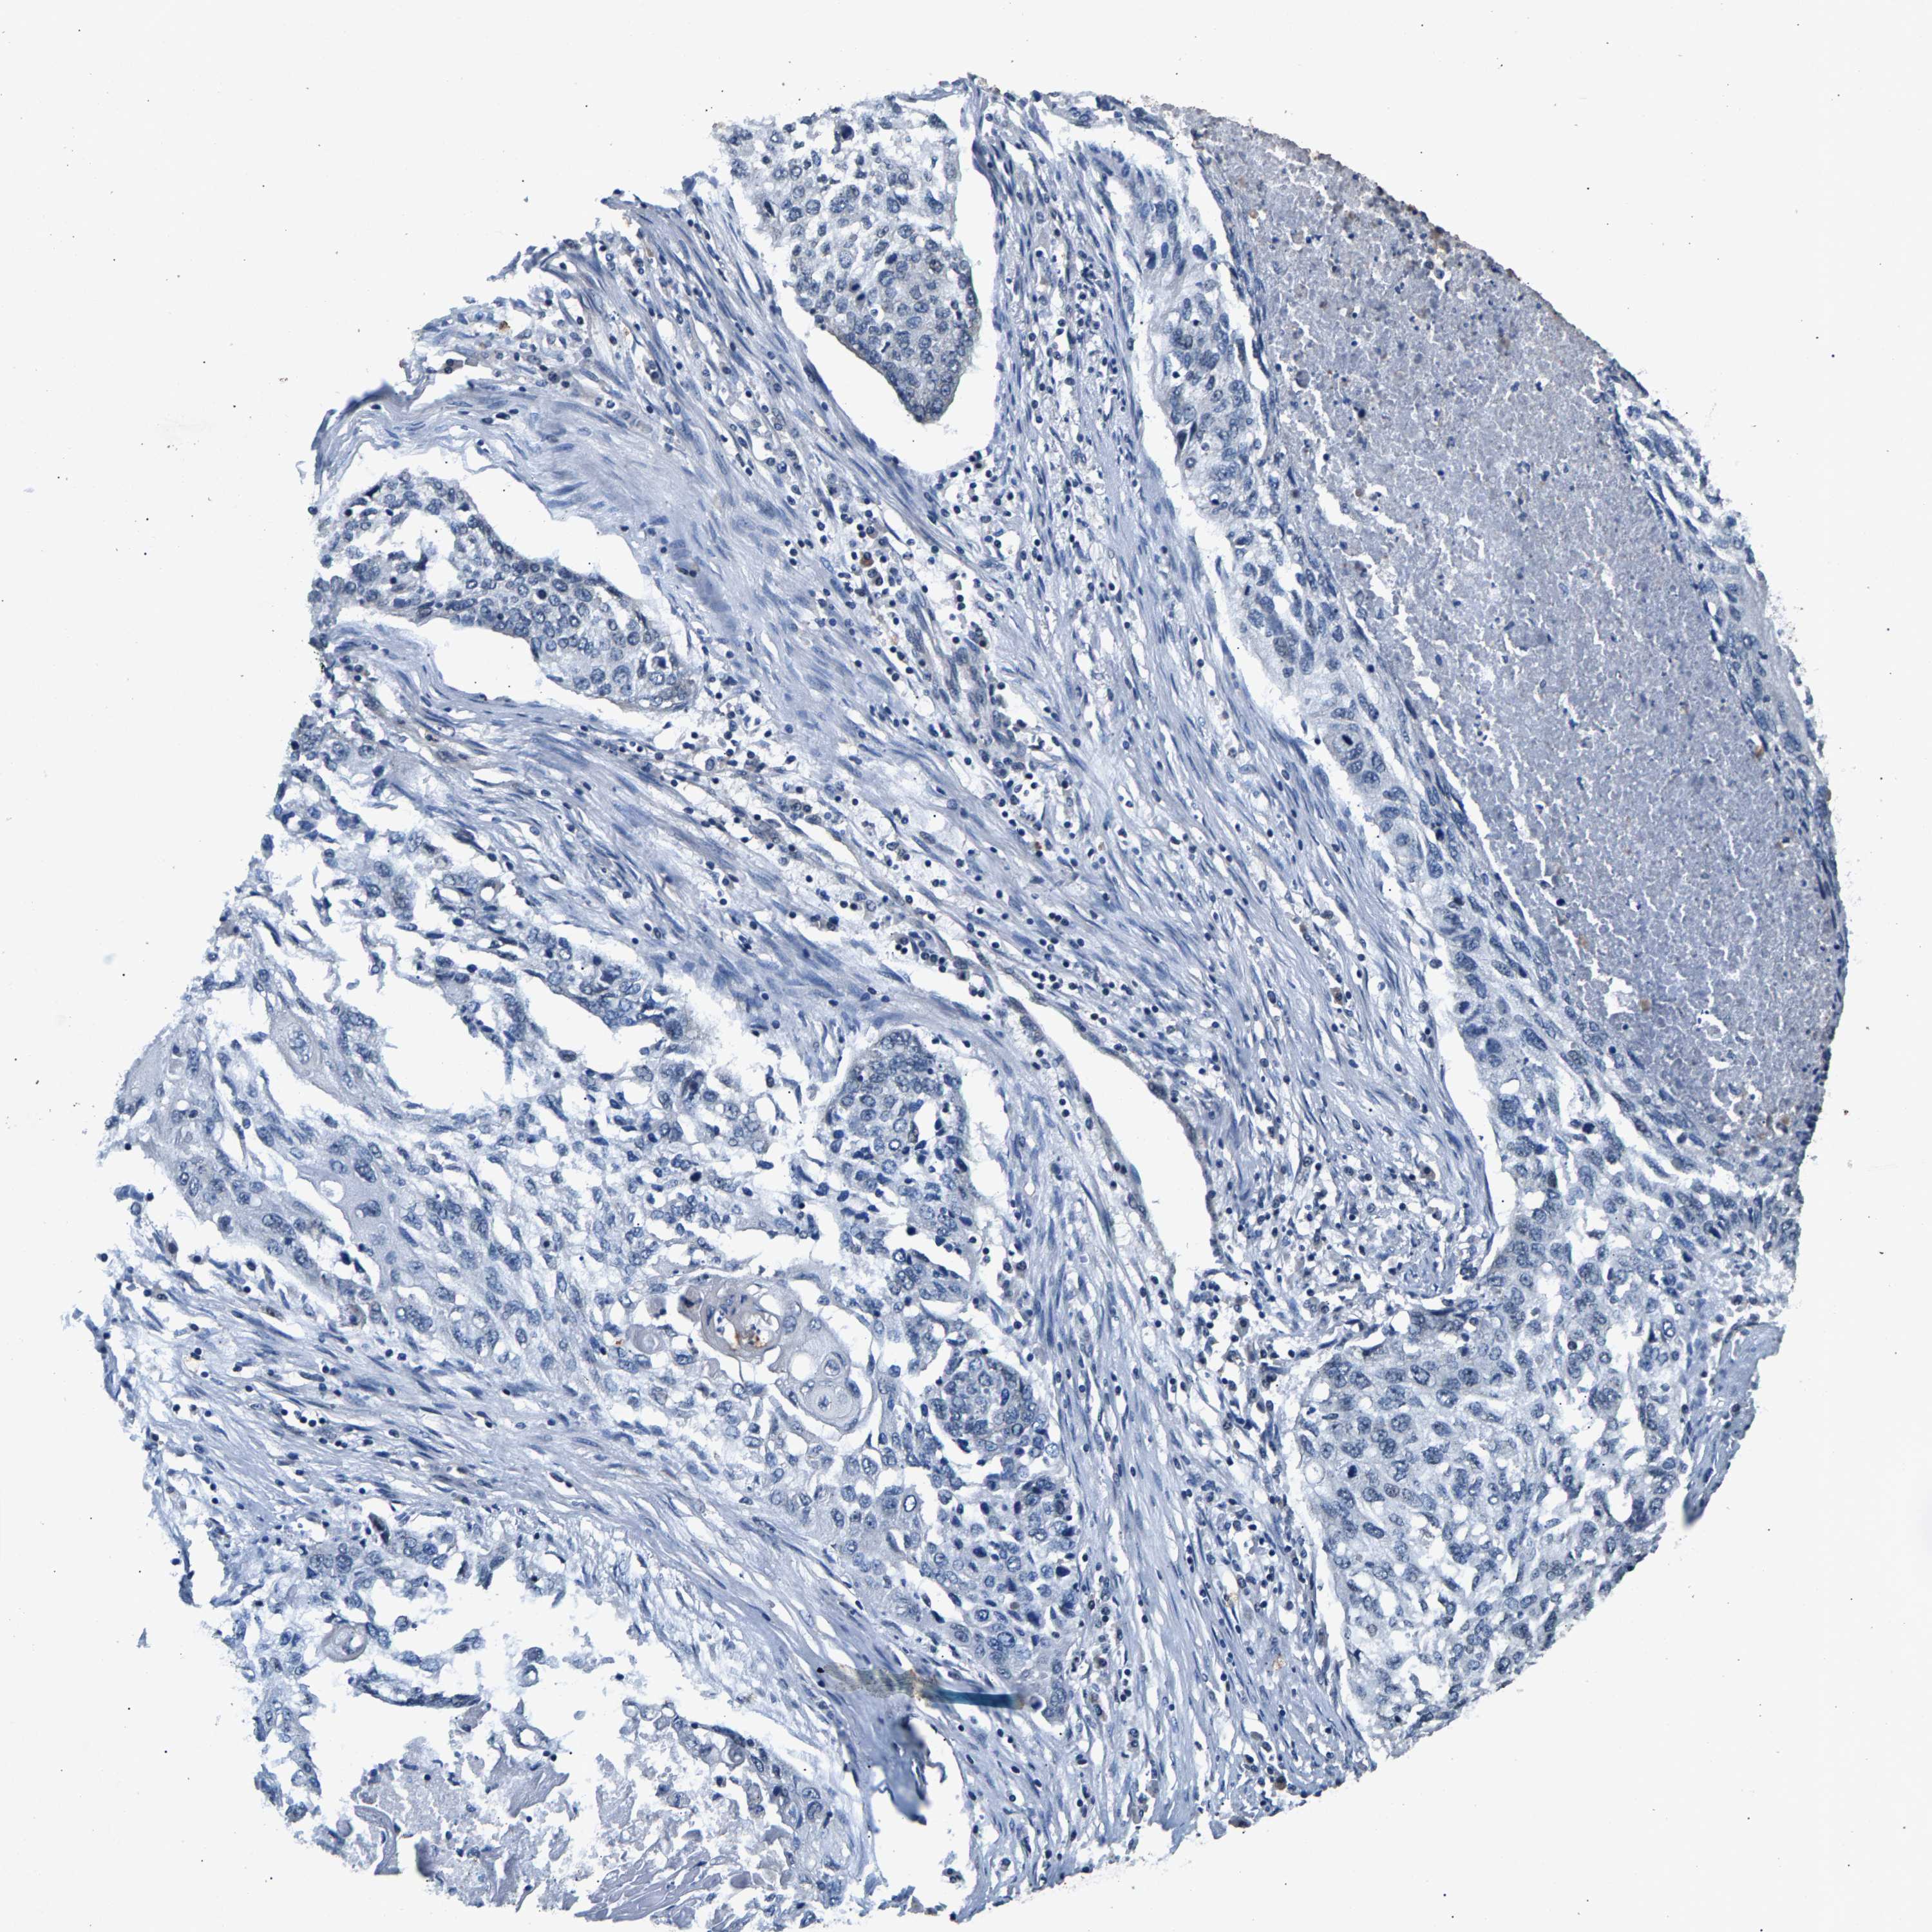

RBM33 is not prognostic in Lung Squamous Cell Carcinoma (TCGA)

: 13.26

P scorei

N/A

Average pTPM 14.0

Number of samples 489